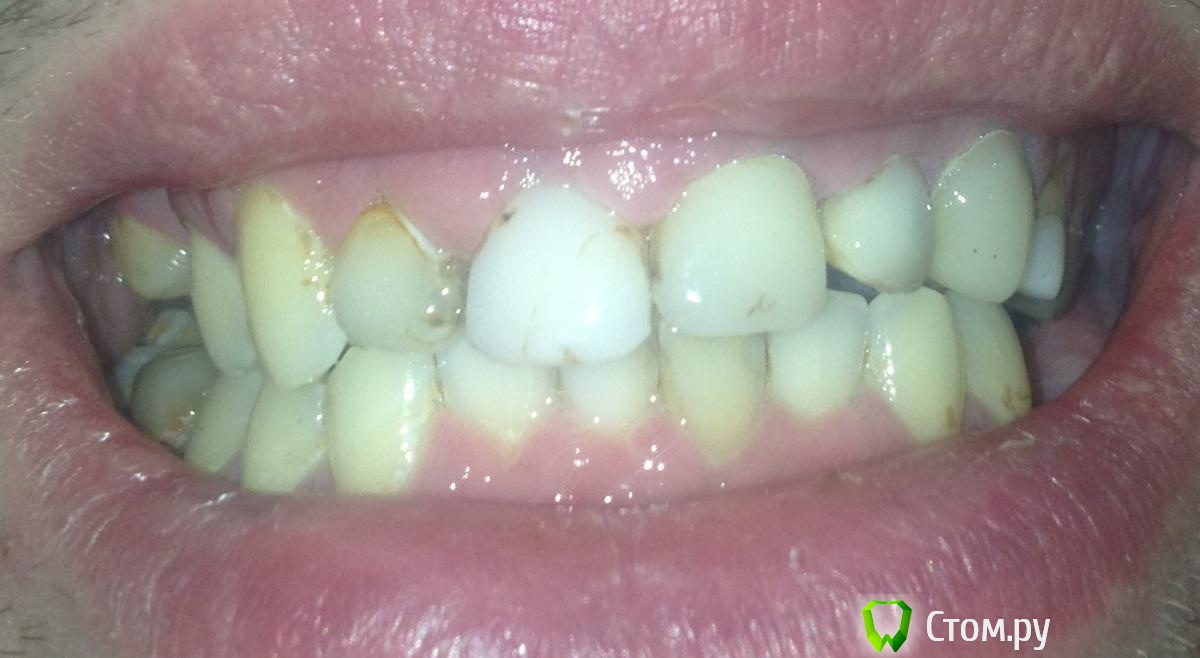

ohspb Опубликовано 7 апреля, 2014 Поделиться Опубликовано 7 апреля, 2014 Здравствуйте. Из за отсутствия 5 и 6 зуба сверху справа, опустилась правая сторона верхней челюсти, кроме того 1 и 2 зубы справа и все остальные слева восстановлены из композита на штифтах. Очень хочется красивую улыбку, в связи с чем собираюсь композит заменить на коронки из диоксида циркония. Требуется ли мне сначала исправить прикус и как это можно в моем случае сделать (Брекеты?). Мой врач ортодонт и протезист в одном, утверждает что брекеты никакие не нужны и желаемого эффекта можно достичь просто поставив коронки. Подскажите как лучше сделать? Зубы запустил из за проблем с деньгами, но сейчас все материальные проблемы решились и нужно все восстанавливать. Фото прилагаю Ссылка на комментарий

ohspb Опубликовано 10 апреля, 2014 Автор Поделиться Опубликовано 10 апреля, 2014 Решил начать с жевательных тогда. Вот снимок прикрепляю Ссылка на комментарий